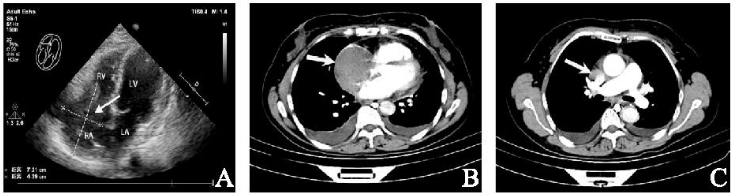

患者,女,59岁,因“活动后胸闷、气紧伴颜面水肿2+月”于2021年1月30日入院。既往史无特殊,体格检查及心电图无明显异常。实验室检查:乳酸脱氢酶334 U/L,血浆D-二聚体3.57 μg/ml, 脑钠肽前体615.4 pg/ml。心脏彩超:右房内可见大小约72 mm×44 mm的不规则团块影(图1 A),可见轻微活动度(考虑血栓?肿瘤黏液瘤?),三尖瓣轻度反流、轻度狭窄,少量心包积液。

胸部增强CT:右心房及上腔静脉内可见斑片状、团块状充盈缺损影(图1 B、1 C)。于2021年2月5日行右房肿瘤切除术,术中见肿瘤大小约8 cm×4 cm, 位于上腔静脉及右心房交界处,向下至右房下部并侵透右房壁,向上延伸至上腔静脉内达左右头臂静脉汇合处下方,上腔静脉内肿瘤尾端有血栓形成。

图1 术前影像学检查。注:A:经胸超声心动图示右心房72 mm×44 mm的不规则团块影(箭头)(十字准线表示尺寸测量值);B:胸部CT示右心房占位(箭头);C:胸部CTA示上腔静脉充盈缺损(箭头)